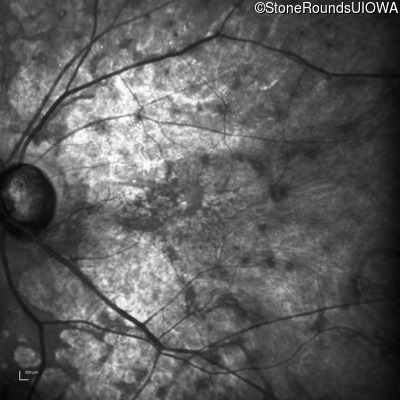

This 81 year old man began using a flashlight to read menus in his 40's. At age 75 his ophthalmologist noticed abnormal fundus findings and referred him to a retina specialist.

Diagnosis & molecular findings

| Late Onset Retinal Dystrophy | C1QTNF5 | Ser163Arg AGC>AGA | AD |